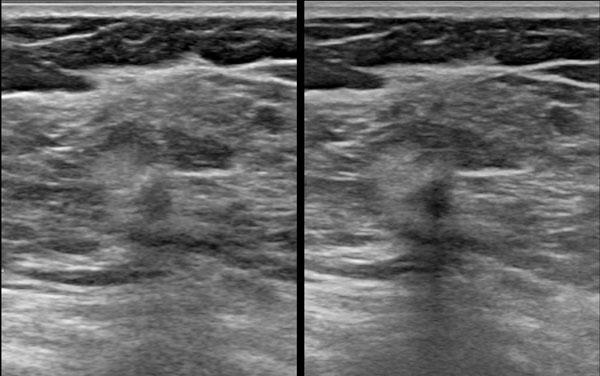

Đây là hai tổn thương hình bầu dục giảm âm.

Thoạt nhìn, chúng trông không khác nhau nhiều.

Hãy quan sát kỹ các hình ảnh và xác định những điểm khác biệt.

Tổn thương bên trái là ung thư biểu mô.

- Hình dạng bất thường

- Bờ góc cạnh và không rõ nét

- Quầng tăng âm xung quanh

- Hướng của tổn thương nghiêng về chiều dọc, không song song với da, tức là chiều cao lớn hơn chiều rộng

- Bóng cản âm phía sau

Tổn thương bên phải là u xơ tuyến vú.

- Hình bầu dục với múi nhẹ

- Bờ rõ nét

- Hướng nằm ngang, song song với da

- Tăng âm phía sau